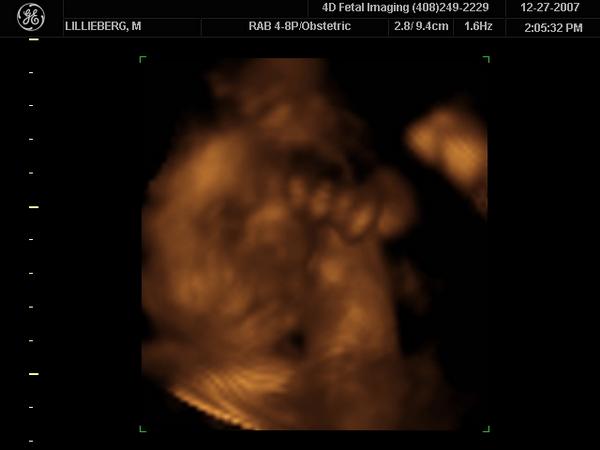

Enjoying Every Moment With My Daughter..

I've already met her.My little Ava.